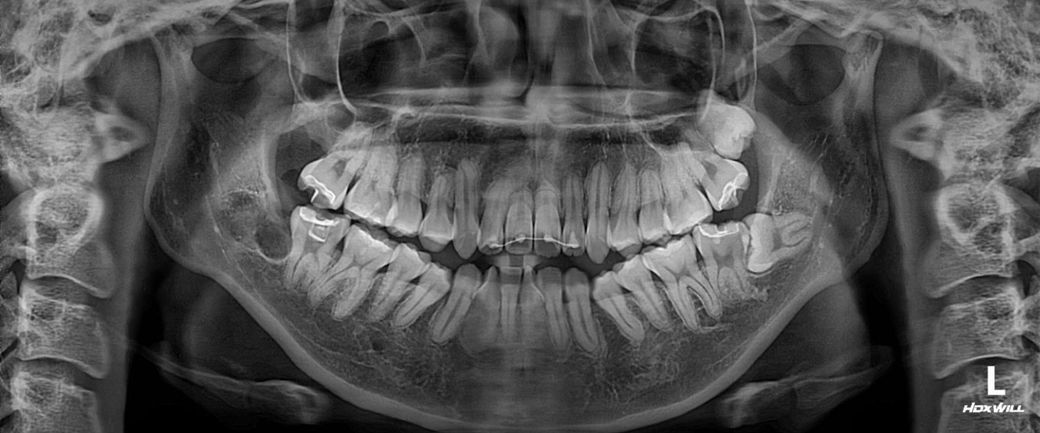

서울 대학병원에서 교정한지 1년여 되가는데요

제가 무슨 퇴행성 턱관절염이 있다고 교정할거면 양악도 해야된다 하셨어요

현재 아래 사랑니 발치까지하고 술전교정을 본격적으로 들어가진 않은것 같습니다 수술이 포함된 치료와 포함되지 않은 단순 교정치료는 결과도 다르고 치료 과정도 다릅니다 빨리 마음이 바뀌었음을 치과의사에게 알리는 것이 좋습니다